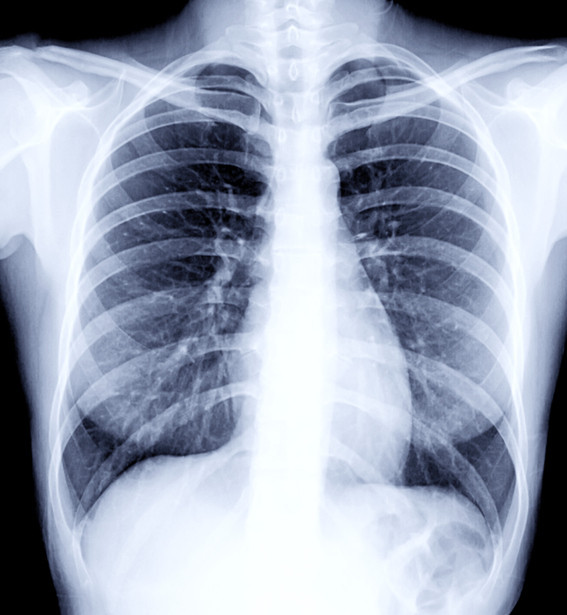

반면, 이미지 데이터(image data)는 2차원 평면에 그려진 시각적 표현물을 말한다. 의학에서는 주로 X-Ray, CT, MRI 등의 데이터가 이미지 데이터이다.